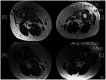

Figure 5-5.

Inclusion body myositis. Skeletal muscle MRI scan of thighs reveals atrophy of muscles and fibrofatty replacement, particularly affecting the vastus lateralis (VL) and vastus medialis (VM) muscles (arrows) with relative sparing of the rectus femoris muscle in between.

Figure 5-6.

Inclusion body myositis. Muscle biopsy reveals muscle fiber with rimmed vacuole and cytoplasmic body inclusions (modified Gomori one-step trichrome stain).

Figure 5-7.

Necrotizing myositis. Muscle biopsy reveals scattered necrotic fibers, some in the process of undergoing phagocytosis. Unlike polymyositis, there is scant, if any, inflammatory cell infiltrate, except in fibers undergoing phagocytosis (hematoxylin and eosin stain).